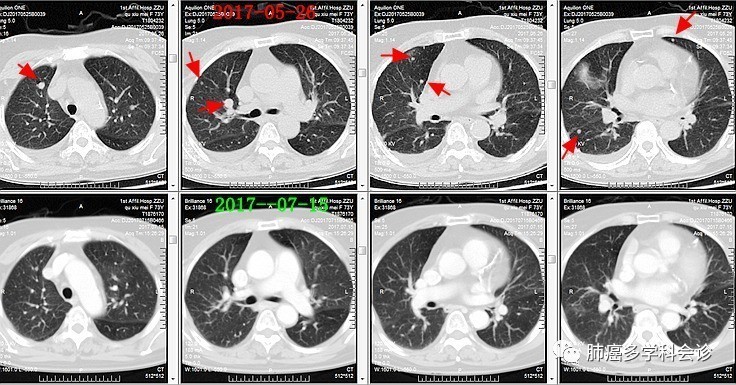

微信图片_20170721110259.jpg诊断为“肾癌多发转移”,阿昔替尼 5mg 每天 2 次连续口服 1 月后,复查CT:右肾肿块明显缩小,双肺转移灶也明显缩小或消失。微信图片_20170721110302.jpg